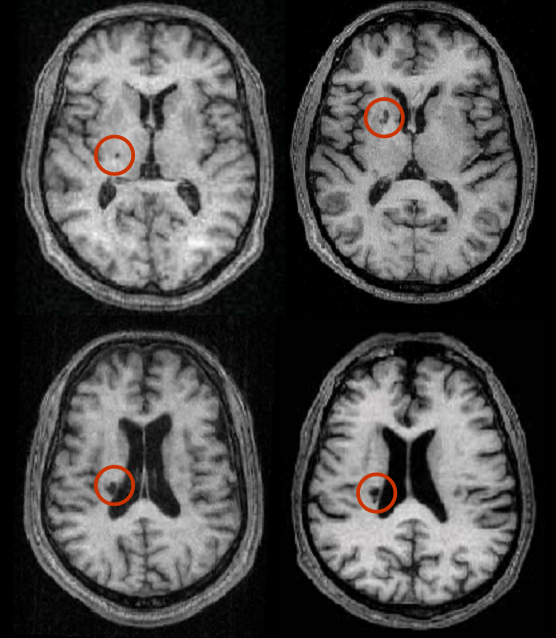

Nhồi máu các mạch máu xuyên: Nhồi máu ổ khuyết

Các hội chứng thường gặp của nhồi máu ổ khuyết (lacunar infarction) là:

- Liệt ½ người thuần tuý

- Mất cảm giác thuần túy

- Liệt nửa người thất điều

- Hội chứng nói khó-bàn tay vụng về

- Không có các dấu hiệu vỏ não (thất ngôn, động kinh…)